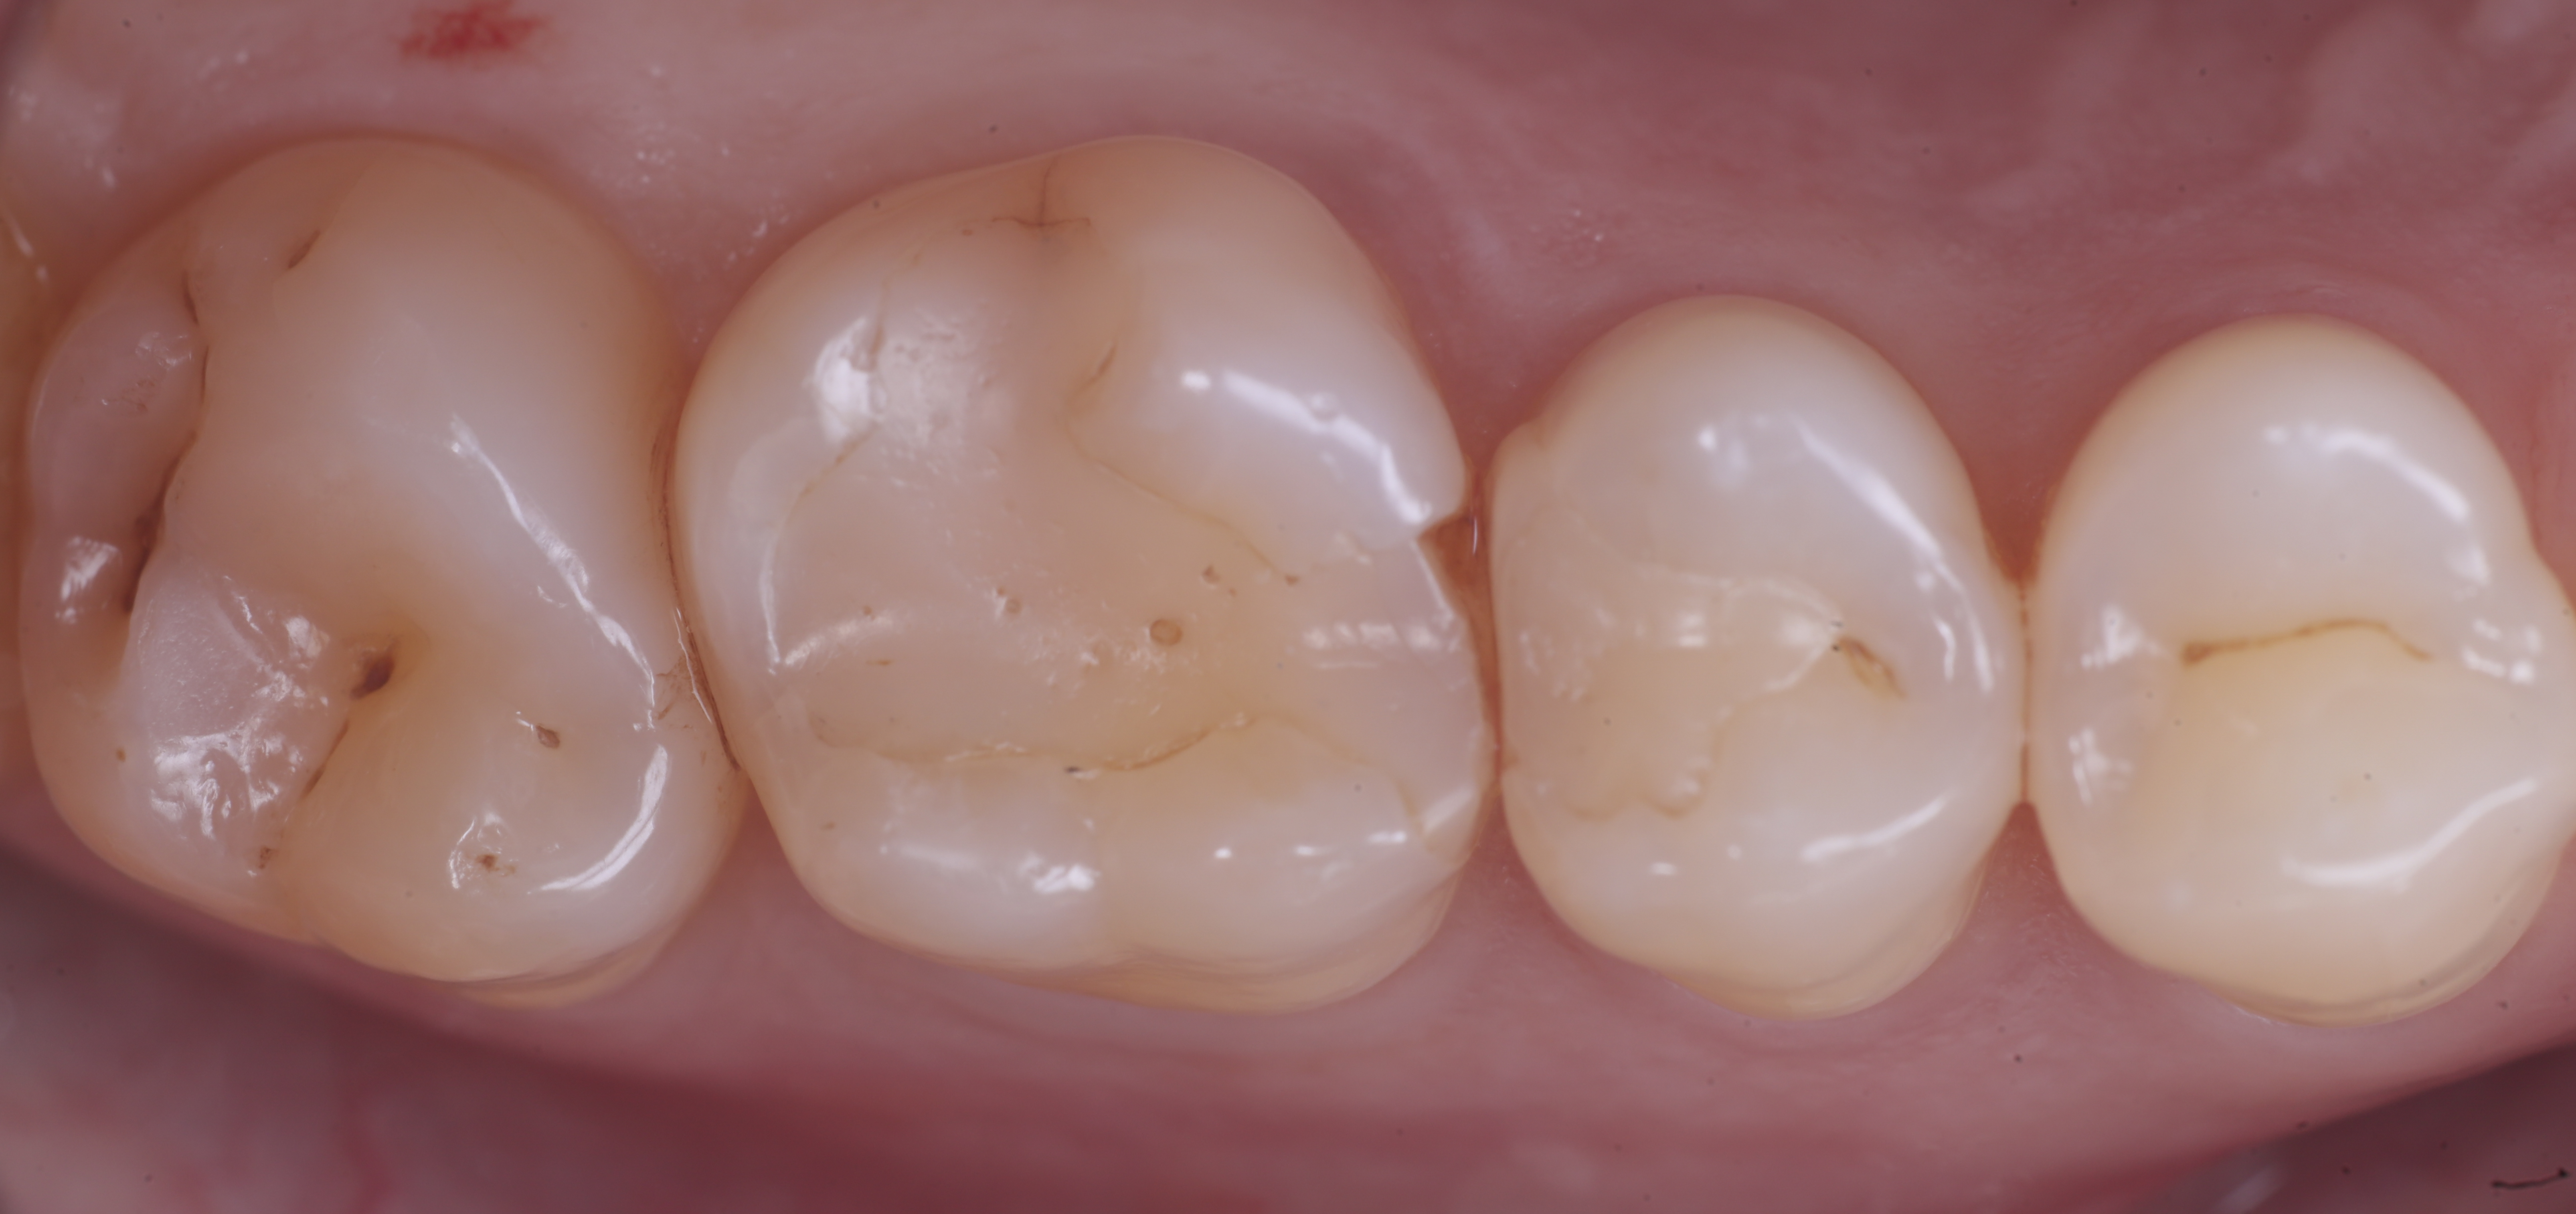

Il paziente in questo caso è una donna di 52 anni che gode di piena salute a livello sistemico.

Si presenta alla nostra attenzione per dolore in zona premolare e molare del primo quadrante. Dopo un’analisi clinica e strumentale con radiografie e test diagnostici, si evidenzia la necessità di sostituire le precedenti otturazioni in composito, al fine di consegnare un migliore punto di contatto (fenomeno dell’impact food).

foto 1 Fotografia iniziale